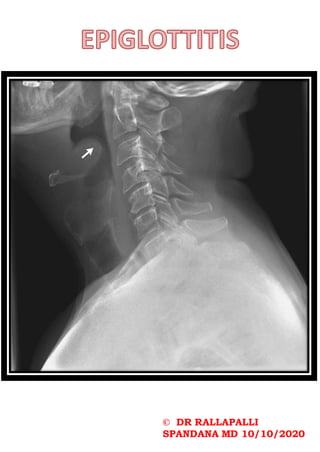

The thumb sign in epiglottitis is a

manifestation of an oedematous and

enlarged epiglottis which is seen on lateral

soft-tissue radiograph of the neck, and it

suggests a diagnosis of acute

infectious epiglottitis. This is the

radiographic corollary of the omega sign.

Thumb sign is a term also used in other

conditions:

•thumb sign (Marfan disease) (also known

as Steinberg sign) : a clinical test in which

the tip of the thumb is visible medial to

the little finger when it is clasped in the

clenched hand

•thumb sign (chordoma): a radiological sign

showing a clival tumour projection

indenting the pons